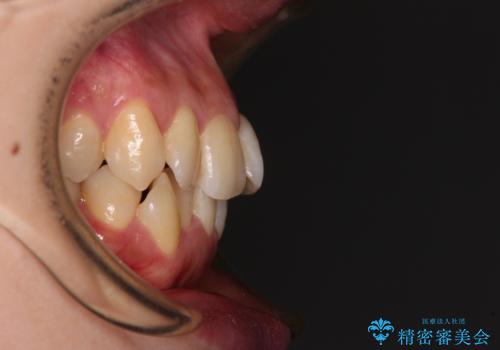

1. 開始前

1. 【モニター】急速拡大装置 狭い歯列を拡大してワイヤー装置で短期間治療の治療前